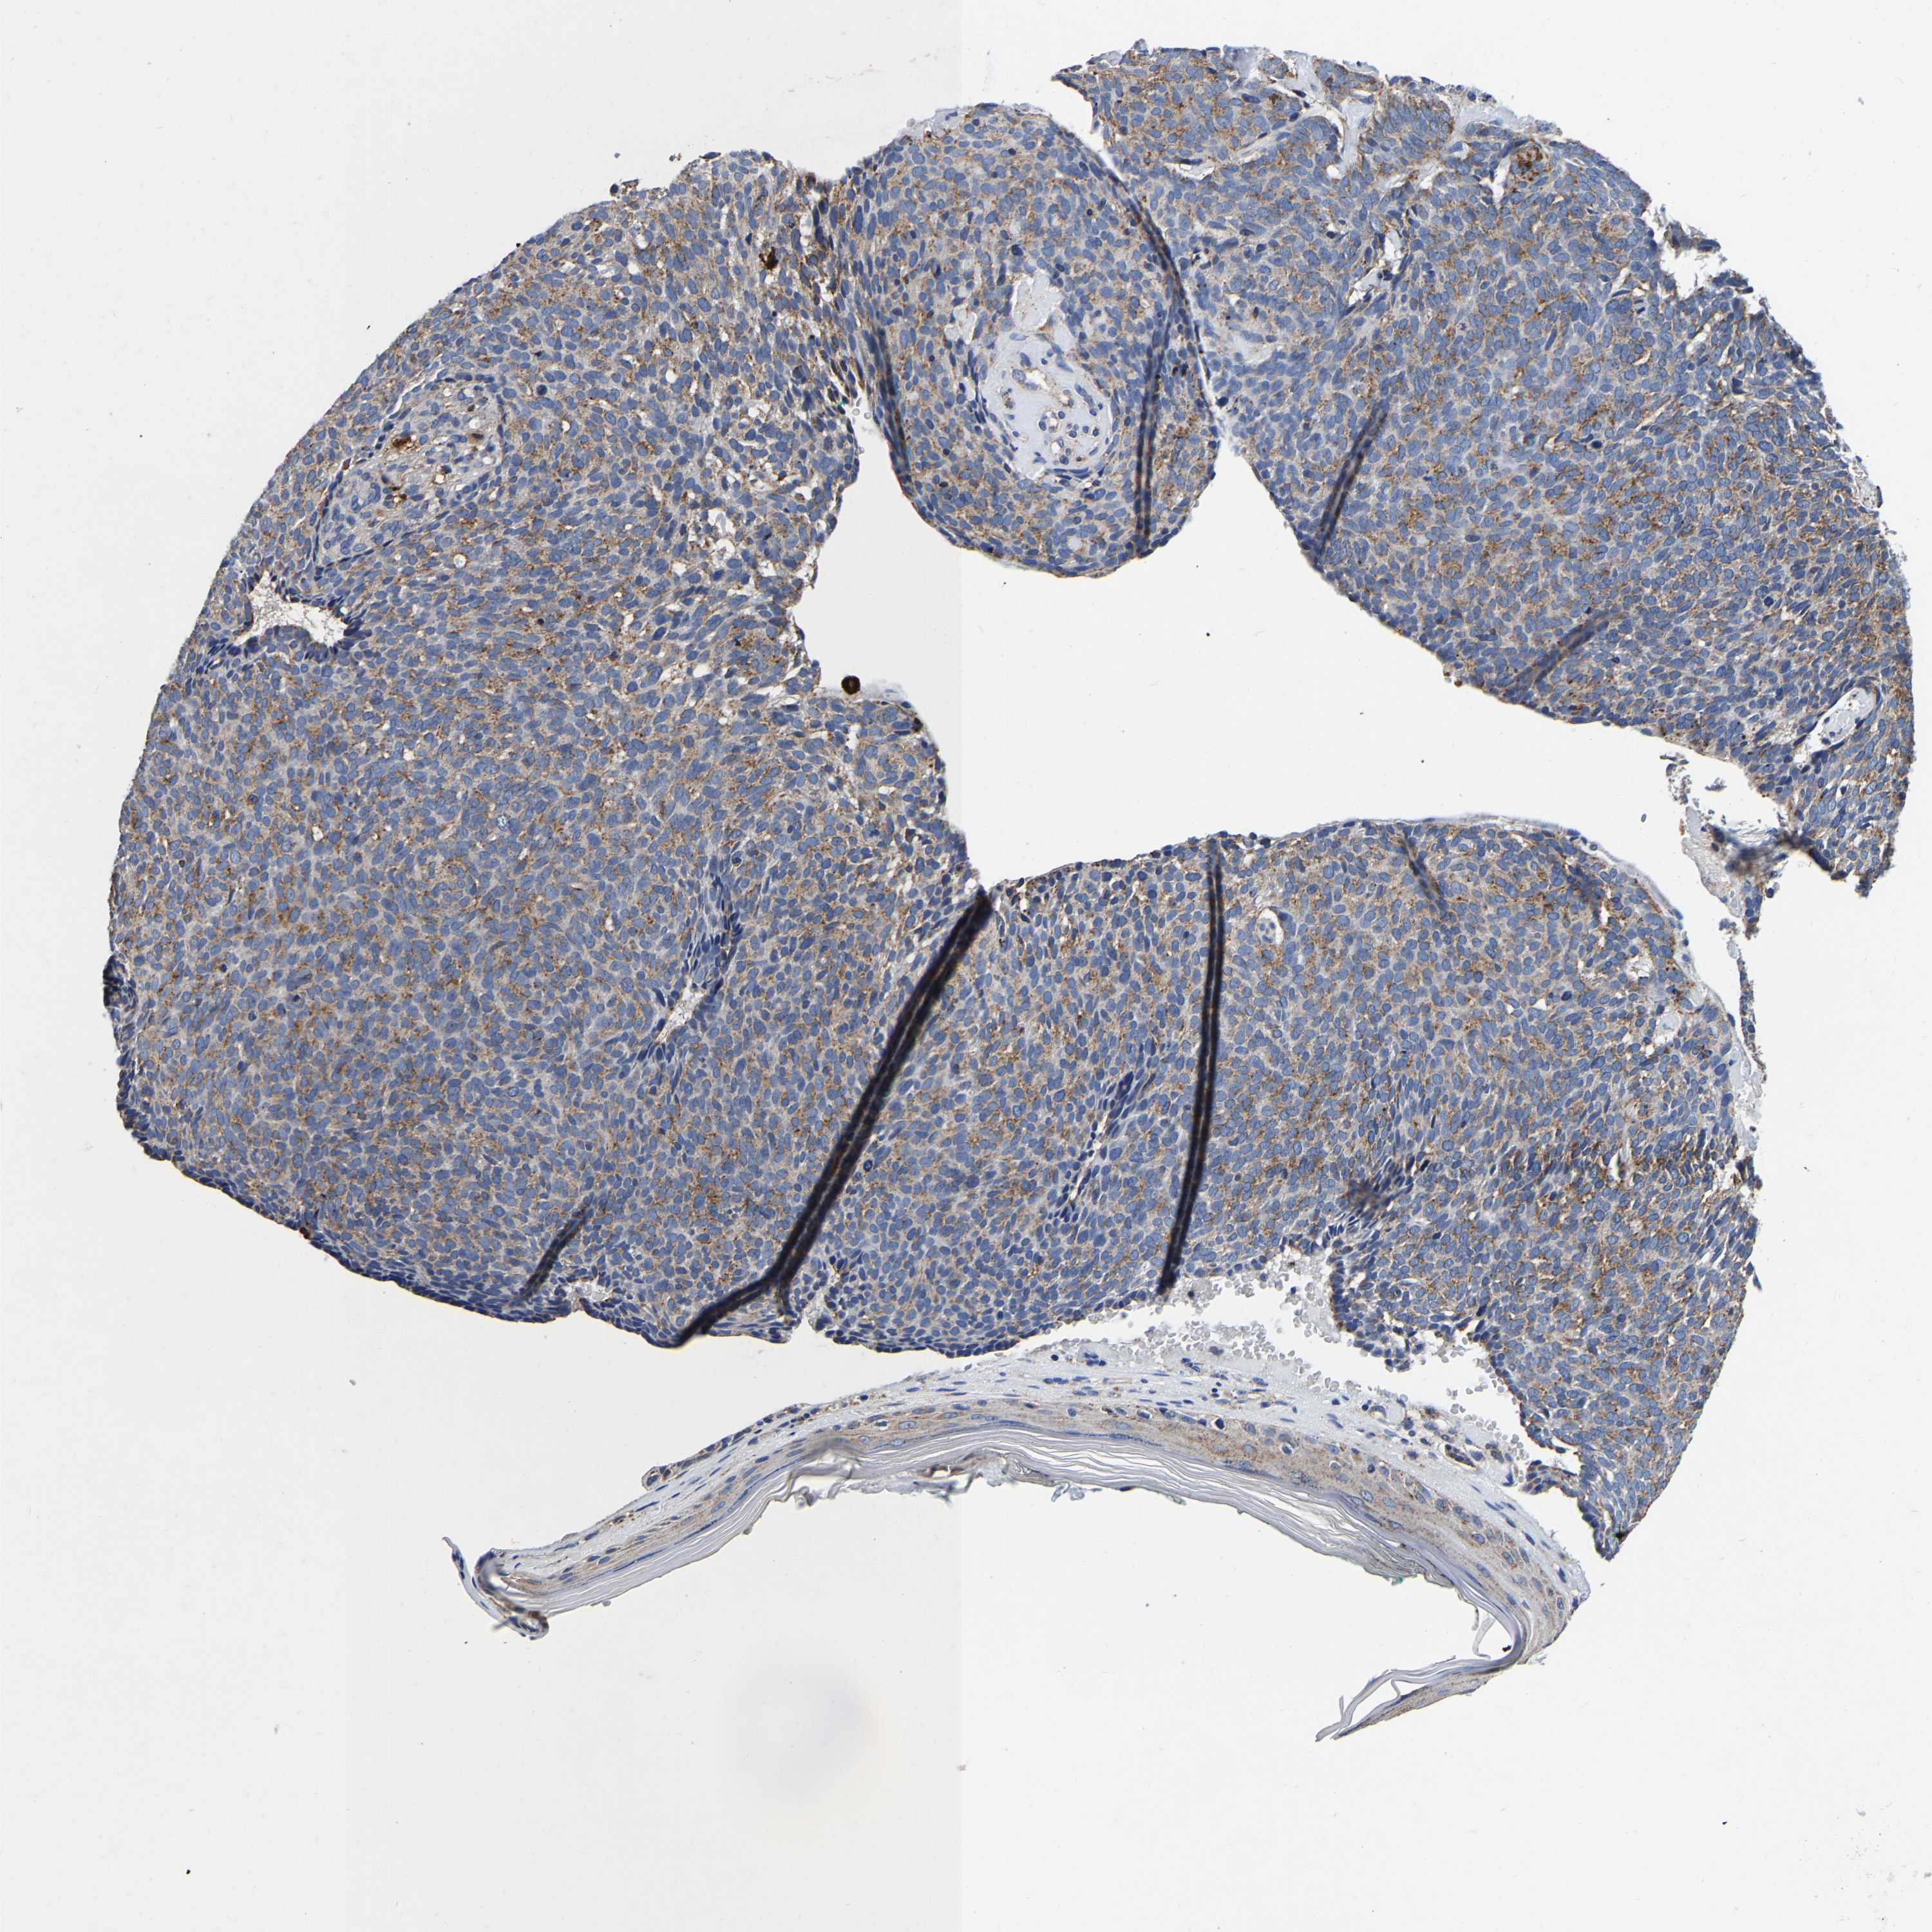

SKIN CANCER - Protein expressioni

A mouse-over function shows sample information and annotation data. Click on an image to view it in a full screen mode. Samples can be filtered based on level of antibody staining by selecting one or several of the following categories: high, medium, low and not detected. The assay and annotation is described here.

Antibody stainingi

Antibody staining in the annotated cell types in the current human tissue is reported as not detected, low, medium, or high, based on conventional immunohistochemistry profiling in selected tissues. This score is based on the combination of the staining intensity and fraction of stained cells.

Each image is clickable and will lead to virtual microscopy that enables deeper exploration of all samples and also displays staining intensity scores, fraction scores and subcellular localization as well as patient and tissue information for each sample.

Antibody HPA008763

Squamous cell carcinoma, NOS